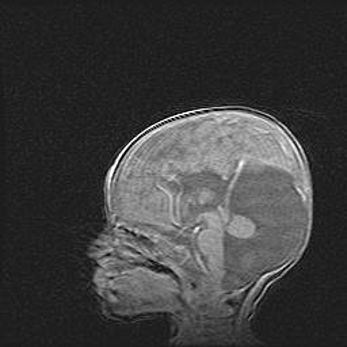

Аномалия Денди-Уокера. Признаки гипоплазии мозолистого тела.

Возраст: 5 месяцев 3 дня

Вес: 5550 г

Пол: мужской

Окружность головы: 39 см

Срок гестации: 40 недель

Аномалия Денди-Уокера – это порок развития головного мозга, для которого характерна триада симптомов: гипотрофия или аплазия червя мозжечка и/или полушарий мозжечка, расширение четвёртого желудочка с формированием ликворной кисты задней черепной ямки, гипертензионная гидроцефалия различной степени.

Гипоплазия мозолистого тела относится к дефектам внутриутробного этапа развития мозговой ткани, возникающим в процессе закладки структур головного мозга, что происходит на начальных этапах развития эмбриона.